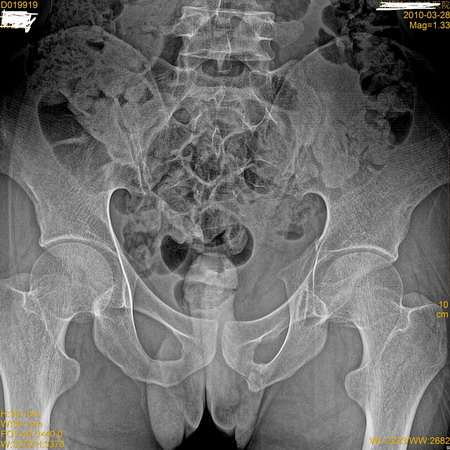

标题: X7185:多处骨折,看看你的眼力!

左侧坐骨结节骨折,左侧髋臼骨折。伴左侧骨盆变形。

左坐骨骨折,左侧髋臼骨折,右髂骨上缘骨折

l5右侧横突骨折?

左侧耻骨下支骨折可能!

左侧坐耻骨支交界处骨折,左髋臼骨折。